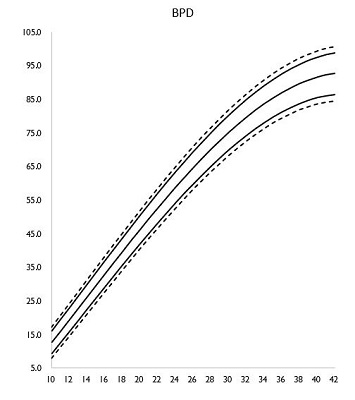

母子手帳「胎児発育曲線 新生児の成長曲線 」の見方と活用法-おむつのムーニー 公式 ユニ・チャーム。

医師監修 胎児の発育曲線 成長曲線 とは?どのように見ればいいの?ゼクシィBaby。

胎児発育曲線ギリギリ成長の小ささで16週から34週まで育ってるべびお君。 - 保育士うたのサイト。

胎児発育曲線』とは?週ごとの発育の目安を助産師が解説◎ - 株式会社エバーセンス。

胎児発育曲線』とは?週ごとの発育の目安を助産師が解説◎ - 株式会社エバーセンス。

胎児発育曲線の±2.0SDの意味は?エコー写真に学ぶ統計学 - 日常を少し掘り下げてみる。

医師監修 おなかの赤ちゃんの発育は順調? 「胎児発育曲線」とはトモニテ。

胎児発育曲線の±2.0SDの意味は?エコー写真に学ぶ統計学 - 日常を少し掘り下げてみる。

母子手帳「胎児発育曲線 新生児の成長曲線 」の見方と活用法-おむつのムーニー 公式 ユニ・チャーム。